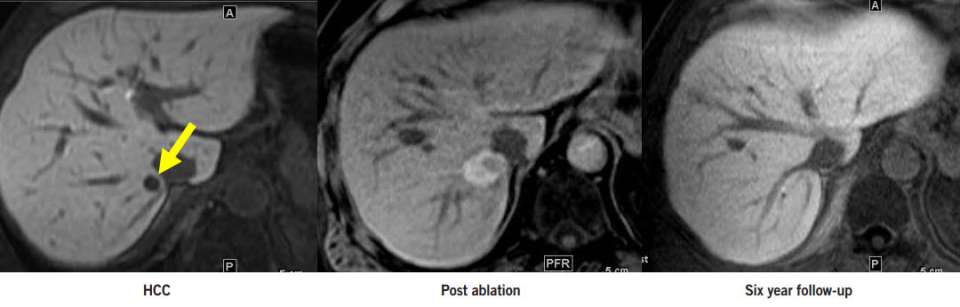

Our physicians are liver specialists in both imaging and minimal invasive therapy. They work in collaboration with the liver surgeons, hepatologists, and liver oncologists to offer treatments either alone or in combination with traditional surgical and medical therapies. Treatment strategy is personalized taking into account individual risk factors and very importantly, the precise extent of tumor and the condition of the underlying liver through imaging assessment. Optimal strategy may include one or a combination of minimal invasive treatments below:

- Thermal ablation (microwave and radiofrequency)